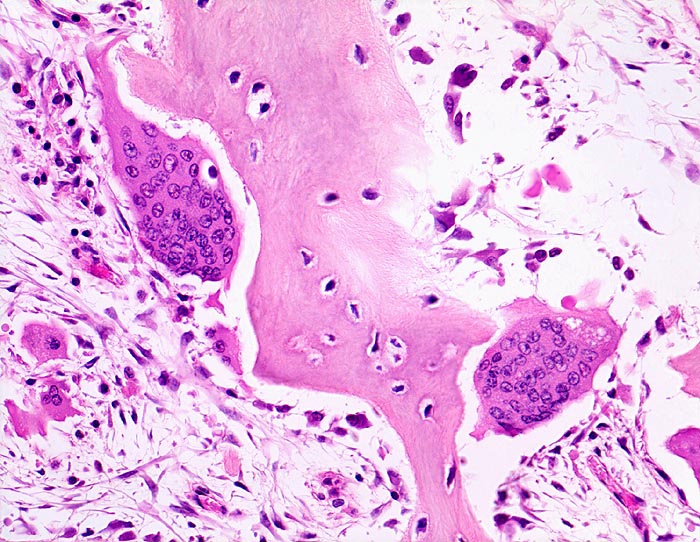

Morbus Paget des Knochens: Osteoklasten

Knochen, Tibia

Pathologisch gesteigerter Knochenumbau: Riesenosteoklasten mit sehr zahlreichen Kernen bauen das Knochengewebe ab. Gleichzeitig finden sich auch vermehrte kubische aktive Osteoblasten, welche Knochen anbauen. Das Mark zeigt eine lockere Fibrose.

Die Patientin hatte wiederholt über Knieschmerzen geklagt. Autoptisch zeigte das Kniegelenk eine leichte Arthrose. Aus der auffallend verdickten Tibia wurde eine Gewebsprobe zur Untersuchung entnommen.